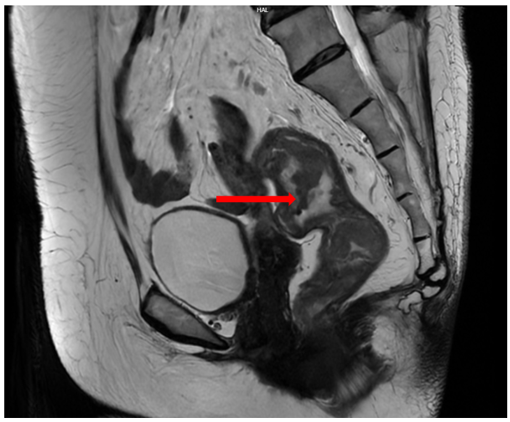

Cộng hưởng từ (MRI) vùng tiểu khung (07/2024):

Hình ảnh dày thành không đều quanh chu vi ở trực tràng cao–đoạn đầu đại tràng sigma; dày nhất khoảng 12 mm, trên đoạn dài khoảng 45mm; mất cấu trúc lớp thành ống tiêu hóa, kèm thâm nhiễm tổ chức mỡ xung quanh. Lân cận có vài hạch, hạch lớn khoảng 14×9 mm (tổng <7 hạch).

Hình 3: MRI vùng tiểu khung

MRI tiểu khung: Hình ảnh dày thành trực tràng giữa giảm còn trên đoạn dài 27 mm, chỗ dày nhất 8 mm; không thấy thâm nhiễm xung quanh, giảm so với 07/2024.